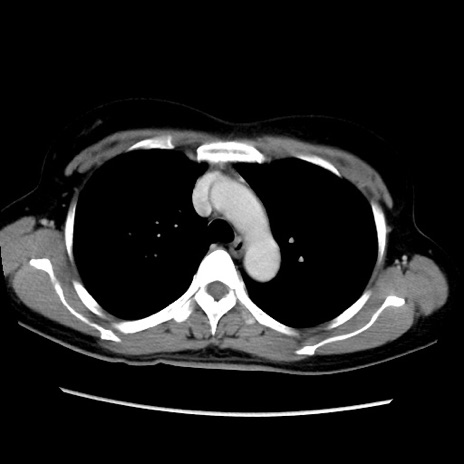

症例39(横断像)

【症例】40歳代女性

【主訴】上下腹部痛

【現病歴】2日目から下腹部痛あり。夜間は痛みで眠れなかった。昨日より上腹部痛と下痢が出現。臥位で痛みは軽快したため、休んでいた。本日になって臥位でも立位でも痛みが強くなってきたため救急要請。

【既往歴】子宮内膜症

【身体所見】部:平坦・軟、左上下腹部に圧痛あり、反跳痛あり。

【データ】WBC 21800、CRP 26.78